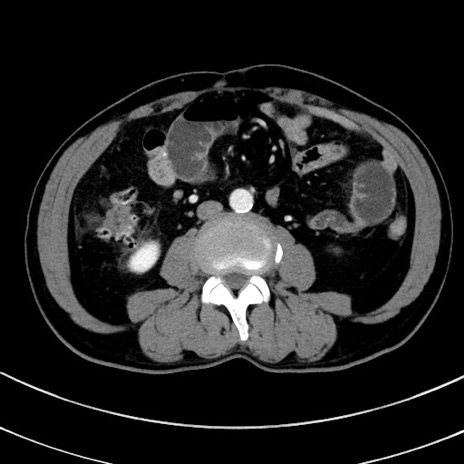

症例8(横断像)

【症例】 60歳代男性

【主訴】 黒色吐物

【現病歴】 4日前から嘔気自覚、2日前の朝食後にも嘔気あり、自分で手で嘔吐反射起こし嘔吐したところ血が混ざっていたため受診。

【既往歴】 5年前汎発性腹膜炎を伴う急性虫垂炎で手術、高血圧、前立腺肥大症、高脂血症

【身体所見】 腹部正中に手術癩痕あり 腹部平坦・軟圧痛なし膨満感あり

【データ】WBC 8400、CRP 4.54